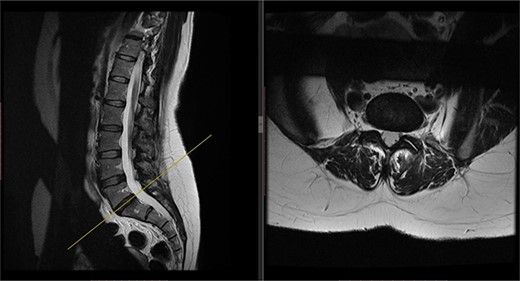

X-rays of the lumbar spine (Fig. 1) and pelvis performed in December 2015 showed a small idiopathic scoliosis in the lumbar spine. A magnetic resonance imaging (MRI) scan was performed in February 2016, which showed non-compressive disc degeneration and disc bulge at L4/5 and L5/S1. She was referred to physiotherapy for rehabilitation.

Preoperative X-ray of the lumbar spine performed in December 2015, confirming small idiopathic scoliosis in the lumbar spine.